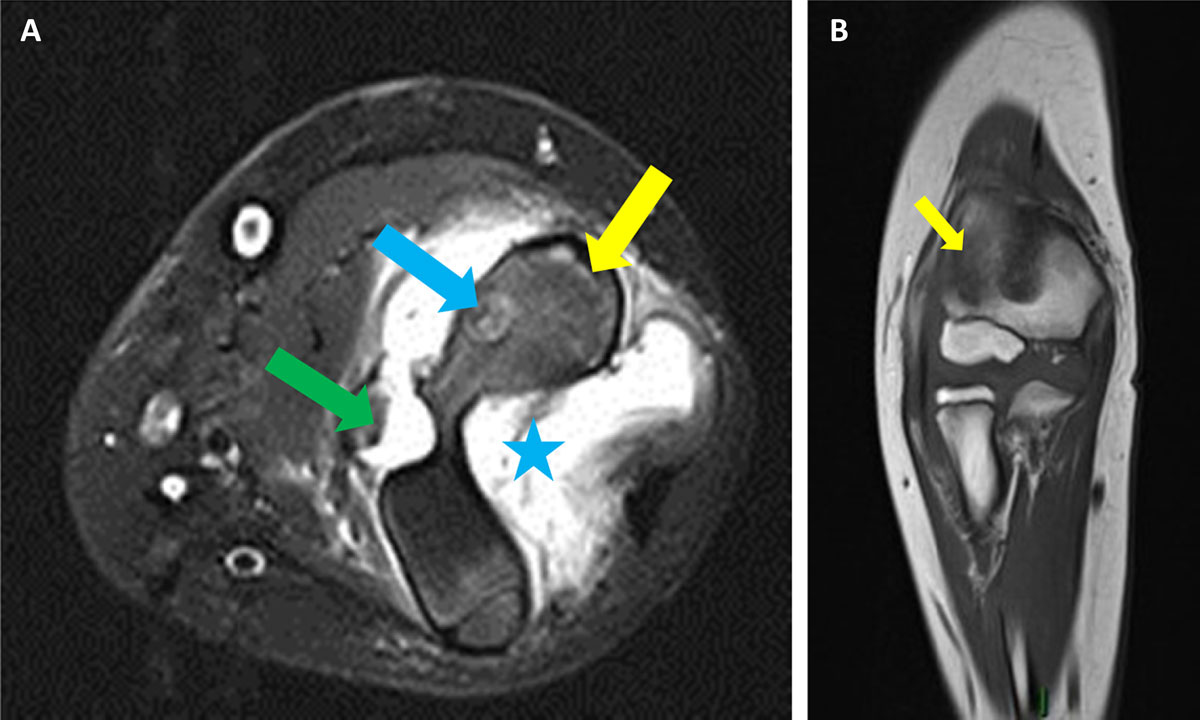

MRI demonstrated joint effusion (blue asterisk on Figure 3A), bone marrow edema in the distal humerus (yellow arrows on Figure 3A, B) and a lesion in the lateral metaphysis with heterogenous signal intensity on T2-weighted images with fat saturation, corresponding to a possible abscess or nidus (blue arrow, Figure 3A). Soft tissues around the joint were infiltrated (green arrow, Figure 3A). These findings were considered suggestive of chronic osteomyelitis or osteoid osteoma. Synovectomy and surgical resection of the focal lesion were performed. Pathological examination finally settled the diagnosis of intra-articular osteoid osteoma (IAOO).

Figure 3